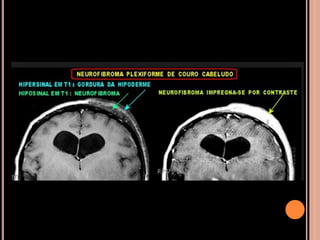

 Neurofibromas:

tu benignos da bainha dos nervos periféricos que

podem se originar desde a raiz dorsal dos gânglios

nervosos até os ramos nervosos terminais de

qualquer nervo;

Cutâneo, subcutâneo, nodular profundo e

plexiforme(NFP);

NF1

NFP

 Crescimento longitudinal ao longo dos nervos

 Até em 50% dos pacientes com NF1

 10% sofrem transformação maligna;

 Neurofibromas iso ou hipossinal em T1 e hipersinal

em T2 e intensa impregnação pelo contraste;

“sinal do alvo” em T2;